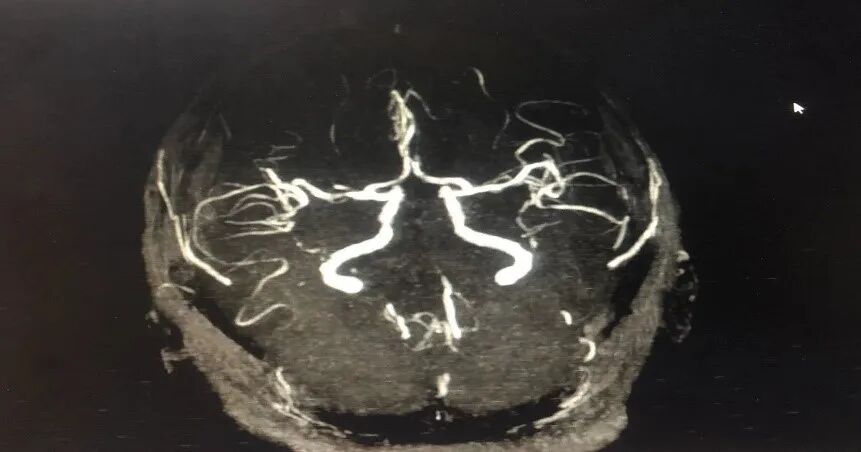

病历夹什么径技·第151期|串联营病历夹:京广连营_https://www.jmylbn.com_新闻资讯_第72张

病历夹什么径技·第151期|串联营病历夹:京广连营_https://www.jmylbn.com_新闻资讯_第73张

病历夹什么径技·第151期|串联营病历夹:京广连营_https://www.jmylbn.com_新闻资讯_第74张

<<滑动查看下一张图片>>

结论:颅脑CT提示左侧基底节、放射冠区腔隙样软化灶。颅脑DWI提示双侧小脑、桥脑、中脑、双侧海马、双侧枕叶、右侧丘脑及右侧胼胝体多发急性脑梗塞。颅脑MRA提示基底动脉及双侧大脑后动脉未见显示;右侧大脑中动脉中-重度狭窄;脑动脉硬化。初步诊断为急性后循环脑梗死,基底动脉闭塞。